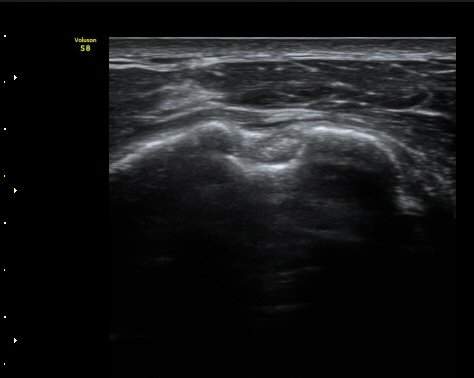

ÀÌµÎ¹Ú±Ù°Ç È¾´Ü¸é°Ë»ç¿¡¼­ °ÇÁÖÀ§¿¡ ¼Ò·®ÀÇ ¼ö¾×Àú·ù¿Í Á¡¾×³¶³» ¾×Àú·ù°¡ °üÂûµÈ´Ù(»çÁø 1, 2).